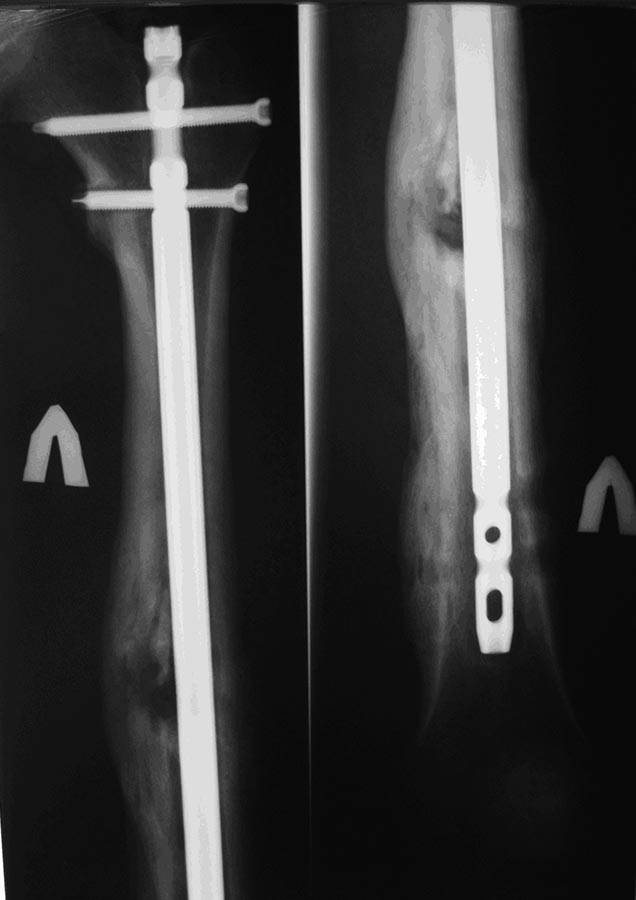

Пациент после БИОС бедренной кости.

Пациент 26 лет, около года назад получил травму в результате ДТП. По

поводу перелома диафиза бедренной кости выполнялся БИОС. Заживление ран

в области дистальных блокирующих винтов происходило вторичным

натяжением, однако, в ходе местного лечения раны зажили. Спустя 4-5 мес.

пациент обратился с болями в нижней трети бедра (проекция дистальных

блок. винтов). При RG выявлена их миграция, выполнено их удаление.

Какова дальнейшая тактика? 1. ничего не делать 2. Удалить

стержень + приливно-отливное дренирование.= 3. Удалить стержень +_ АБ

спейсеры или АБ стержень 4. Удалить стержень + приливно-отливное

дренирование, а затем Цементные АБ импланты.